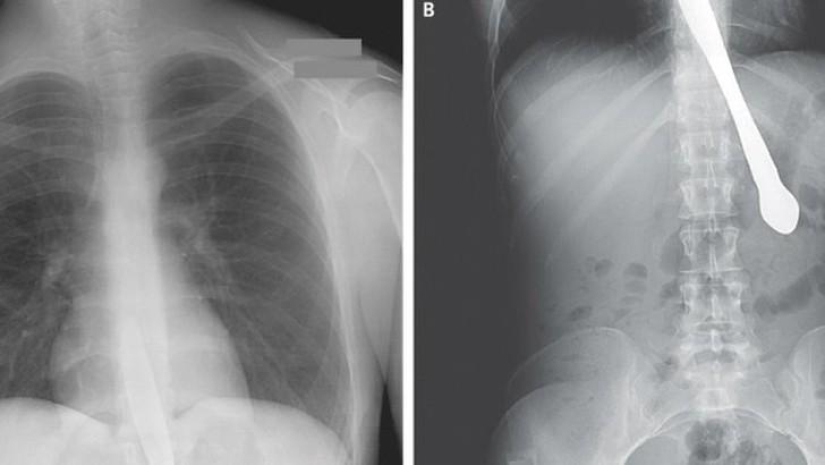

Tijeras.